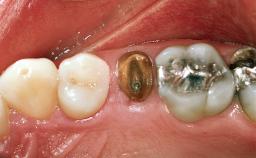

In 2004, an 84-year-old female patient presented at our practice with a hopeless prognosis for her maxillary right first and second premolars. These teeth were supporting a three-unit fixed dental prosthesis and had a cantilevered pontic replacing the first molar. Both teeth had combined endodontic and periodontal lesions, with significant bone loss in the area. The patient also had a large maxillary sinus apical to the first molar site. The patient presented with normal facial form and upon normal smiling, she displayed the affected area. She reported mobility and pain with mastication. The fixed dental prosthesis displayed severe mobility and could be depressed into the alveolar sockets. Exudate was evident around both abutments. There were no significant medical problems reported and the patient reported taking no medications.